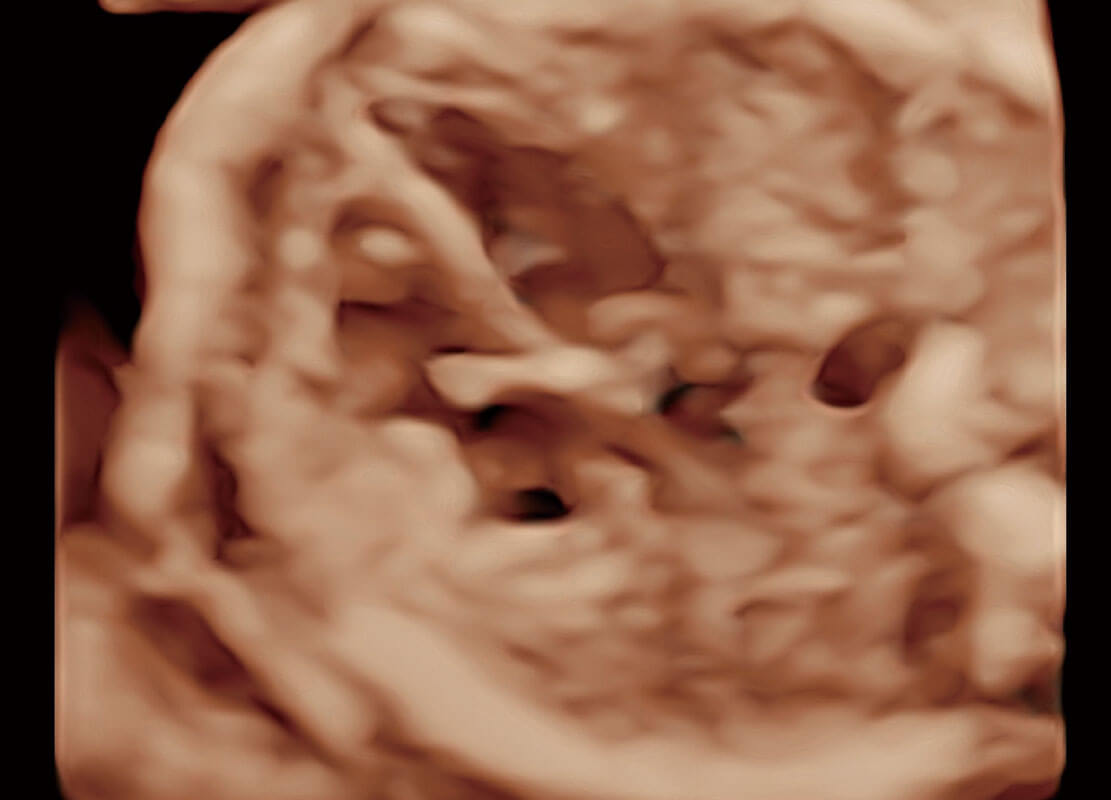

P60提供简单易学易用的高端诊断工具,为您中晚孕筛查提供快速清晰的解剖信息。

S-Fetus能够助您在实时扫查过程中自动识别标准切面、自动测量并录入报告。一个按键,即可快速、高效地获取胎儿生理指标,简化您的产科检查操作。